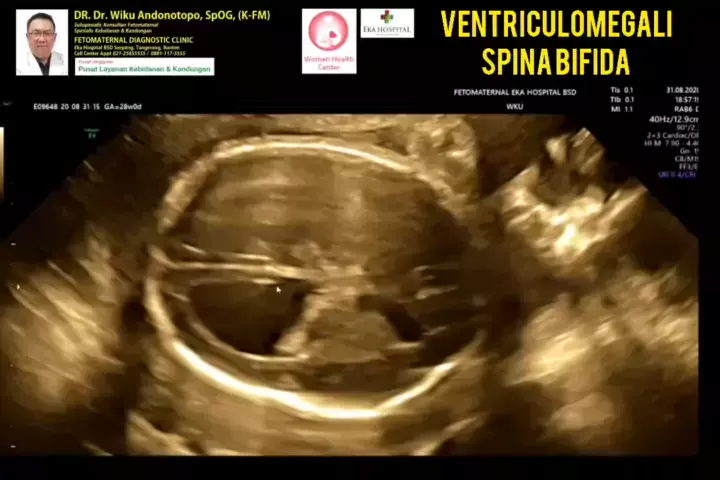

Ventriculomegali kepala dan spina bifida .... #ventriculomegaly #spinabifida #drwikuandonotopo #polikandunganekahospitalbsd #ekahospitalbsd #ekahospitalcibubur #ekahospitalpekanbaru #ekahospitalbekasi #usgfetomaternal #fetomaternal #konsultanfetomaternal #fetomaternalgrandfamilypik #fetomaternalrsiafamilypluit #grandfamilypik #rsiafamilypluit #fetomaternalpurwokerto #fetomaternalpontianak #fetomaternalsurabaya #fetomaternalbali #fetomaternalsemarang #fetomaternaljogja #fetomaternalsolo #fetomat...